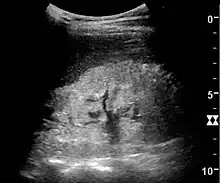

Ultrasound

Kidney ultrasonography is useful for diagnostic and prognostic purposes in chronic kidney disease. Whether the underlying pathologic change is glomerular sclerosis, tubular atrophy, interstitial fibrosis, or inflammation, the result is often increased echogenicity of the cortex. The echogenicity of the kidney should be related to the echogenicity of either the liver or the spleen (Figure 22 and Figure 23). Moreover, decreased kidney size and cortical thinning are also often seen and especially when disease progresses (Figure 24 and Figure 25). However, kidney size correlates to height, and short persons tend to have small kidneys; thus, kidney size as the only parameter is not reliable.[54]

Nephrotic syndrome. Hyperechoic kidney without demarcation of cortex and medulla.[54]